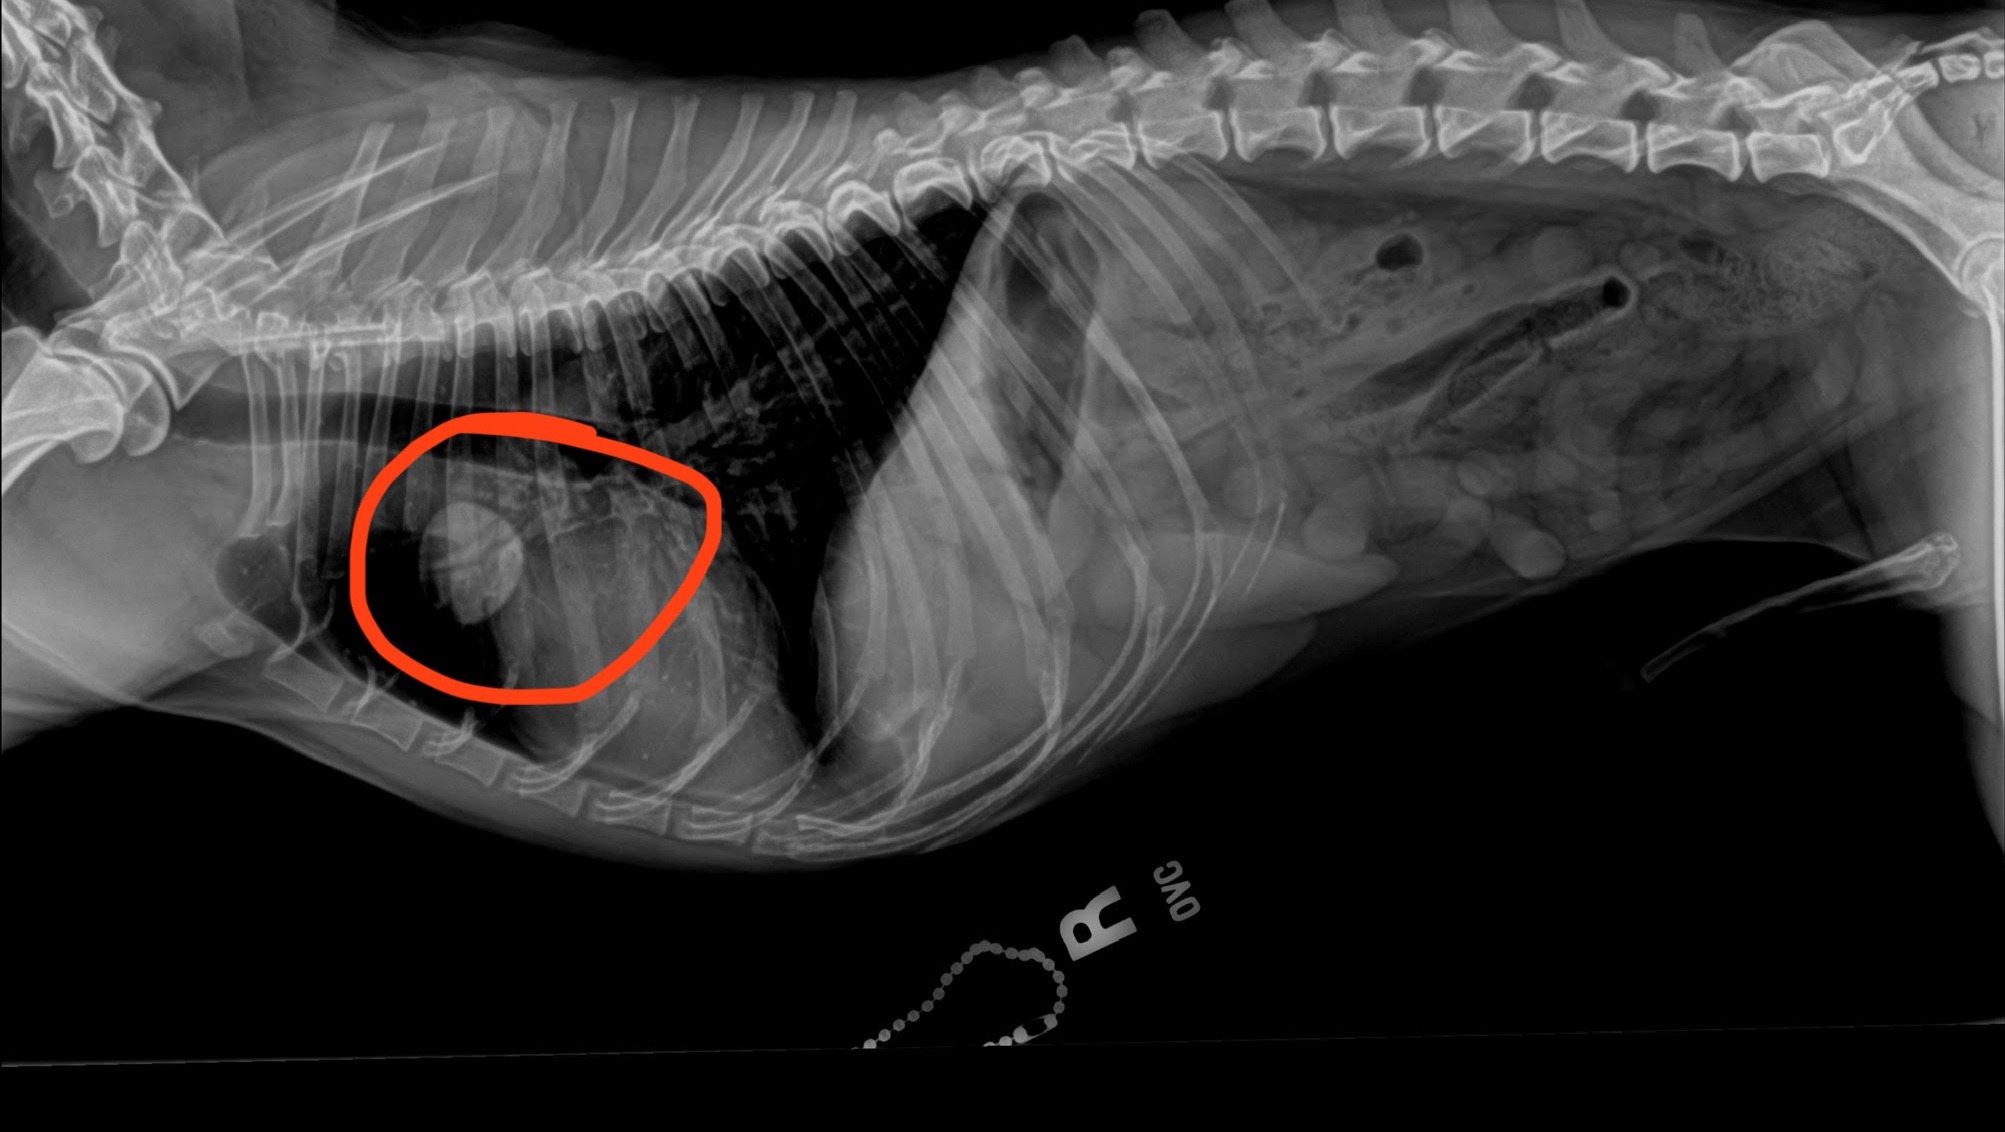

On November 11, 2024, Koa was brought into the clinic for a routine dental under anesthesia. Part of his senior screening included taking x-rays of his chest and abdomen. This is where we first saw the mass in his lungs. His dental was canceled and we performed an abdominal ultrasound which also found a small mass on his liver, and we were suspicious of the findings on his spleen. We were referred to a specialist for a CT scan to determine the next best steps. Our initial worry was that this was a cancer that had spread and made its way from the lungs to the liver and beyond.

Attached, you will find images of the lung mass from the x-rays circled in red. You will also find the image from the abdominal ultrasound confirming the presence of the mass on his liver marked by green lines indicating approximate measurements.